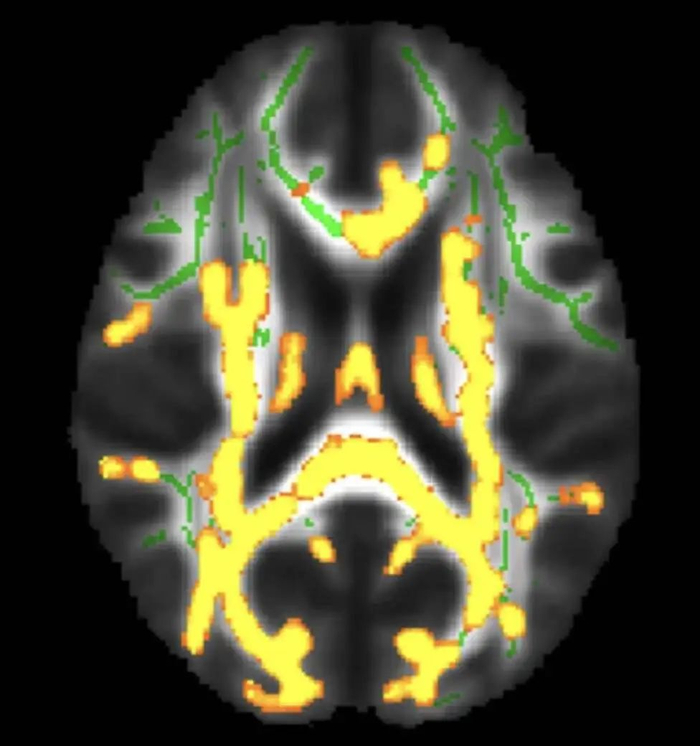

同样年龄的人,腹部脂肪(皮下和内脏)更多,脑部图像显示出更小的脑容量。

左侧红色受试者,四肢和腹部有更多的脂肪(亮色区域),大脑更多黑色空间。图片来源:参考文献 [1]

今年 8 月,来自美国华盛顿大学等 10 个科研机构,纳入了 10,001 名参与者,经过全身核磁、计算机深度学习、回归分析等一通复杂操作后,谨慎得出了结论:

内脏脂肪越多,大脑(灰质、白质等)越小。